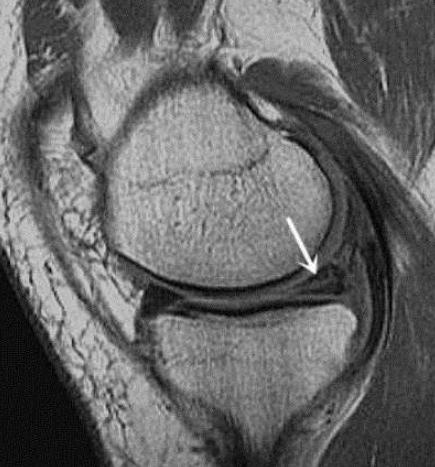

我们先来看看半月板的构造,剖面图显示半月板的特点是外厚里薄,外侧与关节囊相连之处有少量的血液供应,越往关节腔深处靠近,供血量越来越少,甚至无供血。从医学上来区分,有供血的部分我们称之为红区,无供血的部分称之为白区,而在两者之间的部分,称之为红白交界区。

半月板发生了损伤或者撕裂,如果是在红区,因为有有血液的供应,一般情况下手术成功且术后康复效果好,是可以恢复的;

如果是在白区,由于无血液供应,一般情况下,一旦发生损伤或撕裂,几乎不可能自愈。因为这部分的半月板所需要的营养是通过细胞间的相互交换来获取的,而并非靠血液的供应,所以抗击打能力相当脆弱。